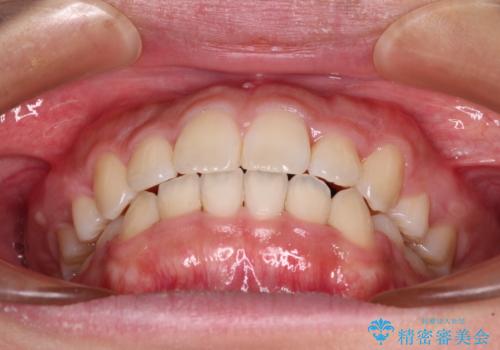

- 前歯のデコボコと口元の突出感を気にして来院された患者様です。

上下左右第一小臼歯4本を抜歯し、ワイヤー装置にて口元を引っ込めるよう矯正治療を行うこととしました。

非常にスムーズに歯列移動が行われ、当初は2-2.5年を予想していましたが、僅か1年4ヶ月で治療を終えることができました。